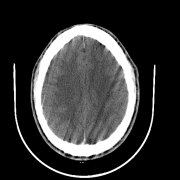

We also include visual examples of consecutive CT slices in Fig. 3. In Scan 1, the baseline Att-MIL produces a wrong prediction at scan level. When using SA, the prediction is correct since dependencies between adjacent slices have been learned. In Scan 2, both models produce correct predictions at scan level, but SA-DMIL is more accurate at slice level. This occurs thanks to the SA loss, that turns the attention scores into smoother values and, therefore, avoids random jumps up and down the decision threshold.

| Scan 1 | ![]() |

| Ground truth | Normal | Normal | Normal | Normal | Normal | Normal | ||

| Att-MIL () [15] | ICH | ICH | Normal | ICH | Normal | ICH | ||

| SA-DMIL- () | Normal | Normal | Normal | Normal | Normal | Normal | ||